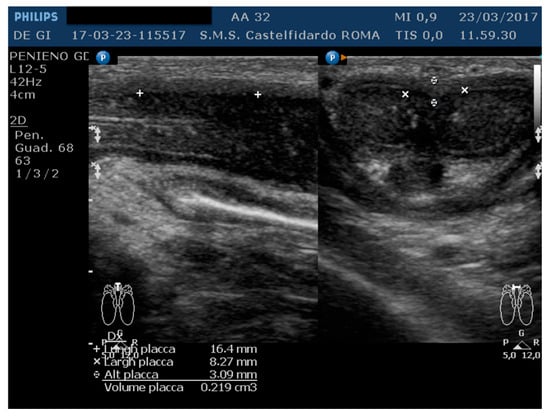

The IIEF score was 26. Physical examination revealed, on palpation of the proximal third of the penis, a nodule measuring about 20 mm in length. A penile Doppler ultrasound was performed (alprostadil 10 mcg). The penile deformity consisted of lateral-left penile curvature (10 degrees). The arterial flow of the cavernous arteries and the end-diastolic velocity were normal: peak-systolic velocity = 95 cm/s (left) and 92 cm/s (right); end-diastolic velocity = 0 cm/s (on both sides). The plaque was located at the base of the penis, its ultrasound aspect was iso-hyperechoic, and it measured 16.4 × 8.27 × 3.09 mm (219 mm3 = volume) (Table 1, Figure 5).

Figure 5. Ultrasonography of the penis before therapy (longitudinal and axial views).